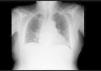

Upon his admission to the service, 24h from the onset of clinical symptoms, an emergency chest x-ray was taken, given the lack of symptom improvement after medical treatment. The lateral projection revealed a foreign body anterior to the ascending aorta (fig. 1), with no consolidation at the base of the right lung (fig. 2). Upper gastrointestinal endoscopy was performed that identified a bivalve shell in the mid-esophagus (fig. 3) with edematous and erythematous esophageal mucosa, and a small ulcer. The shell was extracted with a polypectomy basket, resolving the symptoms.